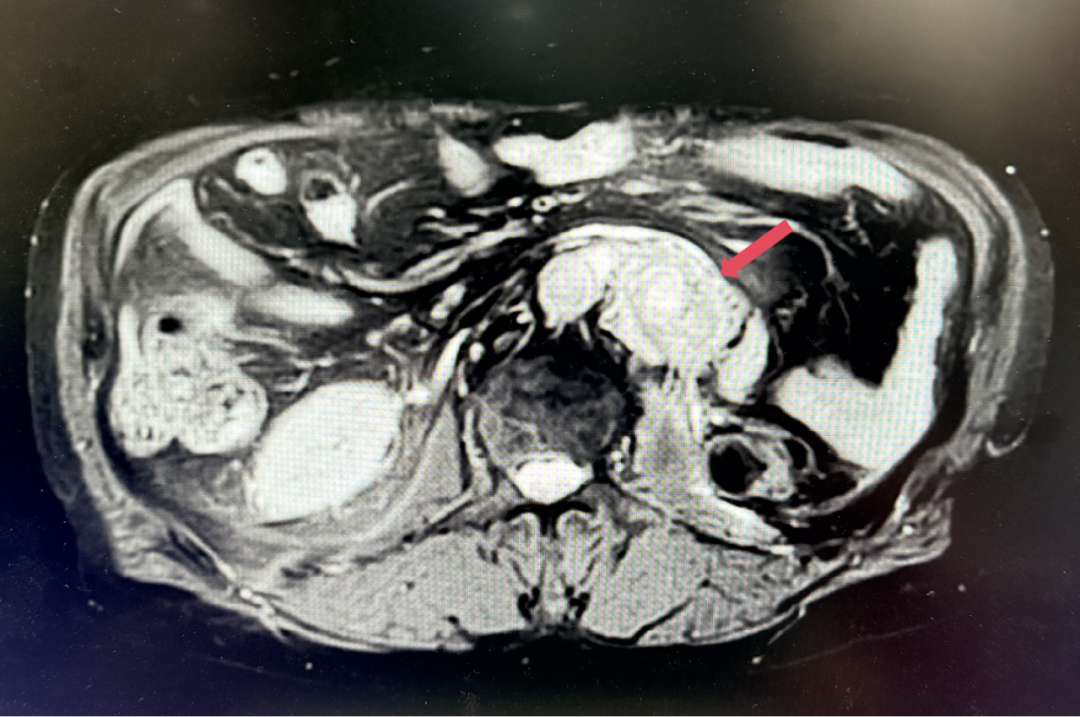

2026年4月:持续维持PR,PFS超过37个月。

患者初诊时68岁,2020年9月因“体检发现左肾占位2年”行腹腔镜下左肾根治性切除术,术后病理提示为肾透明细胞癌,pT3aN0M0,未行术后辅助治疗、未规律复查。2022年3月胸腹盆CT示腹膜后转移,IMDC评分0分,低危组。随后予一线培唑帕尼治疗,最佳疗效SD,2022年11月PD。于2023年1月经筛选进入Ⅲ期FRUSICA-2临床研究,开始接受呋喹替尼联合信迪利单抗二线治疗,用药6周(C2)后首次肿评即实现疗效PR(缩瘤率40.2%),用药10个月时缩瘤率近七成(68%),并维持上述水平至今,PFS已经超过37个月,在二线治疗中实现了长期无进展生存。同时,患者对呋喹替尼联合信迪利单抗方案耐受性良好,仅见轻微蛋白尿和偶然腹泻,未见其他不良反应,也未见免疫治疗相关不良反应。该方案有望为TKI经治的晚期肾癌患者带来新的选择,为实现长期生存提供可能性。